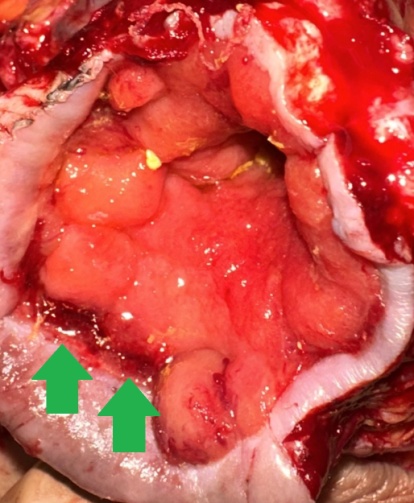

Ακραία φλεγμονή του αριστερού ημικολικού δευτεροπαθώς σε εκκολπωματίτιδα και καλυμμένες διατρήσεις (Ευγενική παραχώρηση Dr. V. Penopoulos)